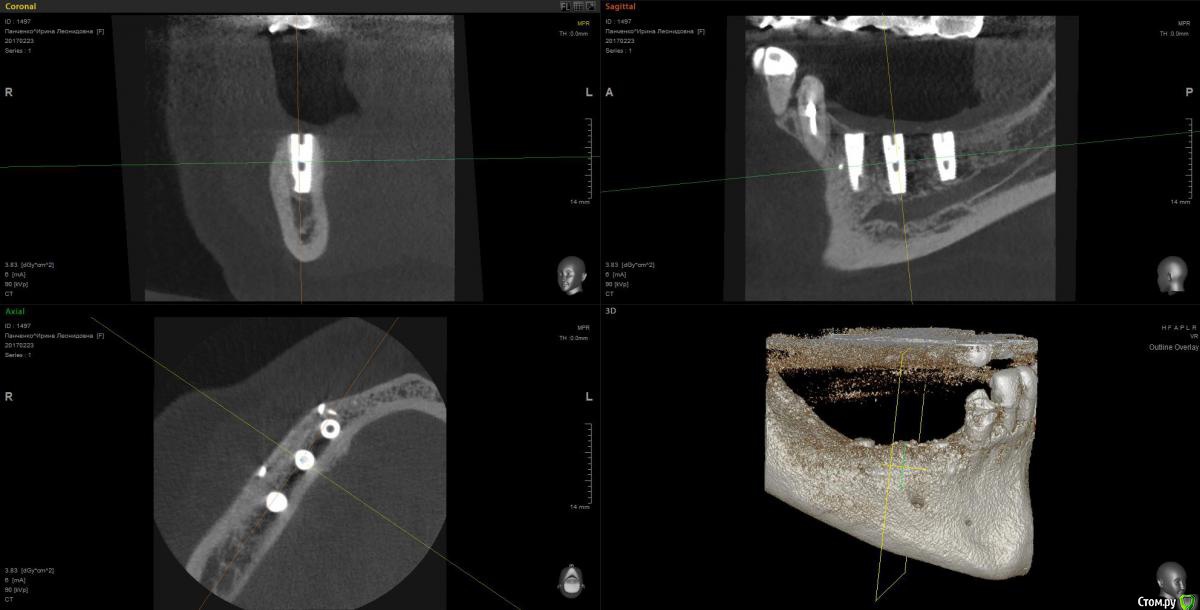

Kostoprav Опубликовано 13 марта, 2017 Поделиться Опубликовано 13 марта, 2017 рецепт сосиски: 70%биопласт by владмива +30%аутокость, мембрана hyprosorb кт до кт сразу после имплантации кт через пол года 3 Ссылка на комментарий